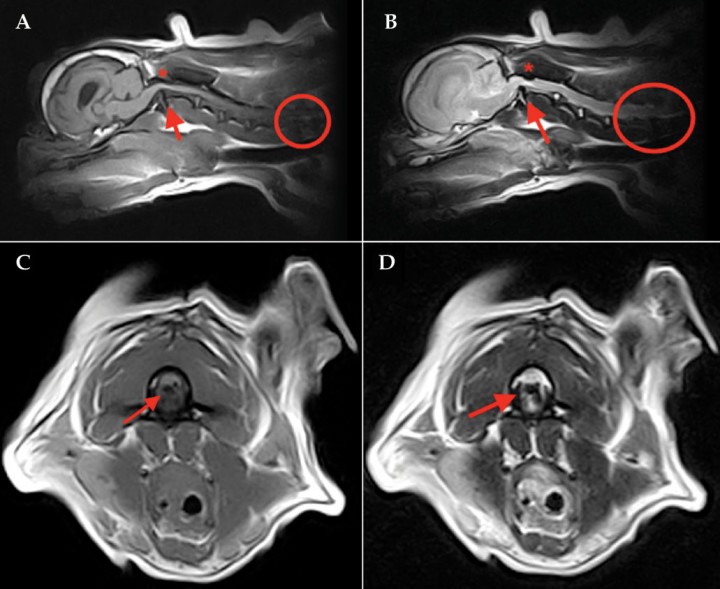

En el caso presentado, se realiza una RM cervical (0.25T, Esaote Grande, Génova) que pone de manifiesto una subluxación C1-C2 (atlantoaxial) con desplazamiento dorsal del diente del axis produciendo una mielopatía compresiva. Además, se observa una compresión dorsal de la médula espinal entre C1 y C2 consistente con una banda dural o una hipertrofia de la membrana atlantoaxial o del ligamento atlantoaxial dorsal. A nivel de C1-C2 se observa una lesión intramedular, de bordes mal definidos, hipertensa (respecto a la sustancia gris) en secuencias ponderadas en T2 y FLAIR, de isointensa a hiperintensa en secuencias ponderadas en T1 y sin realce tras la administración de contraste. Esta señal intramedular es consistente con inflamación o edema. También se visualiza espondilosis y discopatía degenerativa que afecta a los discos C5-C6 y C6-C7 y que se asocia con una leve mielopatía compresiva a nivel de C6-C7. A nivel intracraneal se visualiza una dilatación de los ventrículos laterales, probablemente asociado a la raza (Fig. 1).

<p>Imágenes de RM preoperatoria del paciente. (<strong>A</strong>) Corte en plano medio sagital en T1. (<strong>B</strong>) Corte en plano medio sagital en T2. (<strong>C</strong>) Corte en plano transversal en T1. (<strong>D</strong>) Corte en plano transversal en T2. Se aprecia el desplazamiento dorsal del axis produciendo compresión medular (flechas rojas). Se observa una compresión dorsal de la médula espinal entre C1 y C2 compatible con una banda dural, una hipertrofia de la membrana atlantoaxial o del ligamento atlantoaxial dorsal (asterisco). A nivel de C1-C2 se observa una lesión intramedular, de bordes mal definidos, hipertensa (respecto a la sustancia gris) en T2 y de isointensa a hiperintensa en T1. También se visualiza espondilosis y discopatía degenerativa que afecta a los discos C5-C6 y C6-C7 (círculo rojo) que se asocia con una leve mielopatía compresiva a nivel de C6-C7. A nivel intracraneal se visualiza una dilatación de los ventrículos laterales, probablemente asociado a la raza.</p>

Imágenes de RM preoperatoria del paciente. (A) Corte en plano medio sagital en T1. (B) Corte en plano medio sagital en T2. (C) Corte en plano transversal en T1. (D) Corte en plano transversal en T2. Se aprecia el desplazamiento dorsal del axis produciendo compresión medular (flechas rojas). Se observa una compresión dorsal de la médula espinal entre C1 y C2 compatible con una banda dural, una hipertrofia de la membrana atlantoaxial o del ligamento atlantoaxial dorsal (asterisco). A nivel de C1-C2 se observa una lesión intramedular, de bordes mal definidos, hipertensa (respecto a la sustancia gris) en T2 y de isointensa a hiperintensa en T1. También se visualiza espondilosis y discopatía degenerativa que afecta a los discos C5-C6 y C6-C7 (círculo rojo) que se asocia con una leve mielopatía compresiva a nivel de C6-C7. A nivel intracraneal se visualiza una dilatación de los ventrículos laterales, probablemente asociado a la raza.